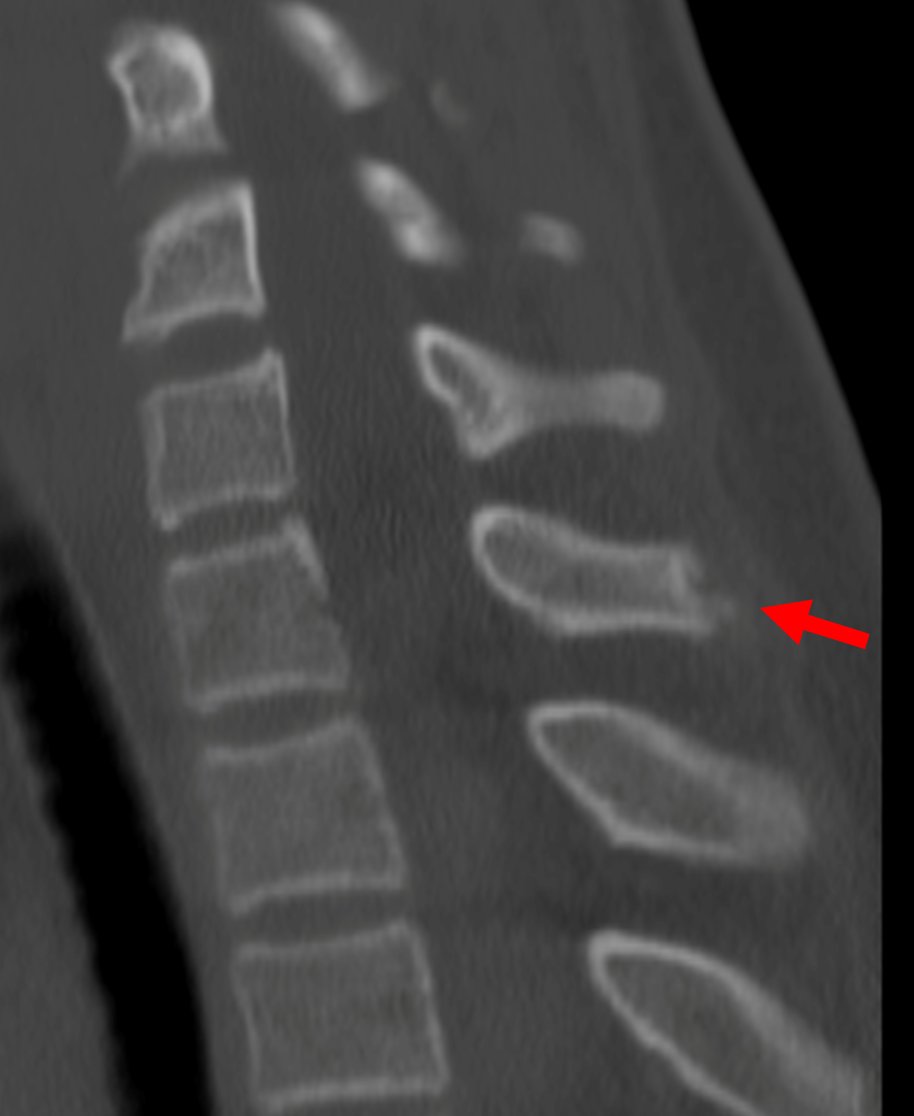

Young gentleman came with severe low back ache following an episode of dengue fever. What do we see here? #spineimaging #medtwitter #radtwitter #FOAMrad #neuroimaging @drvenkimdrd

DrYevSam_Rad's tweet image. Young gentleman came with severe low back ache following an episode of dengue fever. What do we see here?